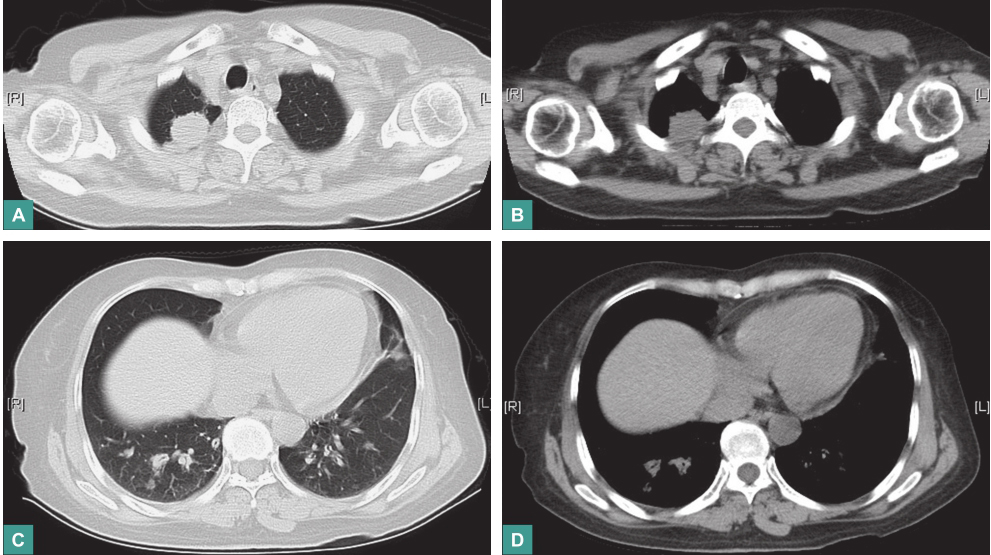

胸部CT:①右肺上叶尖段占位病变,大小约4.0cm×3.1cm,较前明显增大,其内可见空洞;②双侧肺门区及周围新增多发结节状密度增浓影;③纵隔内多发淋巴结肿大(图5)。

图5 胸部CT表现

第一次冲击治疗后复查:

血沉42mm/h,C反应蛋白8.10mg/L。胸部CT:右肺上叶尖段占位病变较前明显缩小,双侧肺门区及周围多发结节状密度增浓影较前有所缩小,纵隔内多发小淋巴结较前有所缩小(图7)。

图7 第一次冲击治疗后复查胸部CT表现